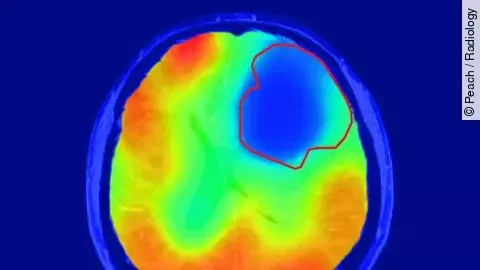

Smart Reporting bietet Softwarelösungen für die medizinische Dokumentation und klinische Anleitung in der Diagnostik. Diese Lösungen sollen Kunden (vor allem Krankenhäuser und Radiologien) helfen, produktiver zu werden, die Qualität zu verbessern und die Kommunikation zu optimieren. Während die aktuelle medizinische Dokumentation hauptsächlich auf handschriftlichen oder eingesprochenen Notizen basiert, stellt Smart Reporting sicher, dass alle gesammelten Diagnostik-Daten für die Analytik zugänglich und mit anderen Systemen ausgetauscht werden können. Diese Technologie ist ein Eckpfeiler für die Präzisionsmedizin. Das Unternehmen hat 2017 mit der Implementierung dieser Technologie in der Radiologie begonnen und inzwischen setzen weltweit mehr als 10 000 Radiologen auf Smart Reporting. Zudem wurde das Start-up kürzlich vom Branchendienst AuntMinnie Europe zum "Best New Radiology Vendor 2020" gewählt.

Erweiterte Bildanalyse und Berichterstattung durch KI

Seit 2019 wird zusätzlich die Befundungslösung für den Bereich der diagnostischen Pathologie angeboten. Darüber hinaus wurden auch erste Anwendungsfälle für eine vollständig integrierte, durch Künstliche Intelligenz (KI) erweiterte Bildanalyse und Berichterstattung in der diagnostischen Medizin realisiert. In zahlreichen Publikationen wurde nachgewiesen, dass die Struktur und Standardisierung der medizinischen Dokumentation sowohl die Behandlungen als auch die Ergebnisse der Patienten optimiert. Die aktuelle Investitionsrunde, die durch Wessel Management unterstützt wurde, wird dazu genutzt, die Technologie weiterzuentwickeln und in verschiedene medizinische Disziplinen, darunter Chirurgie, Onkologie und Kardiologie, zu skalieren.